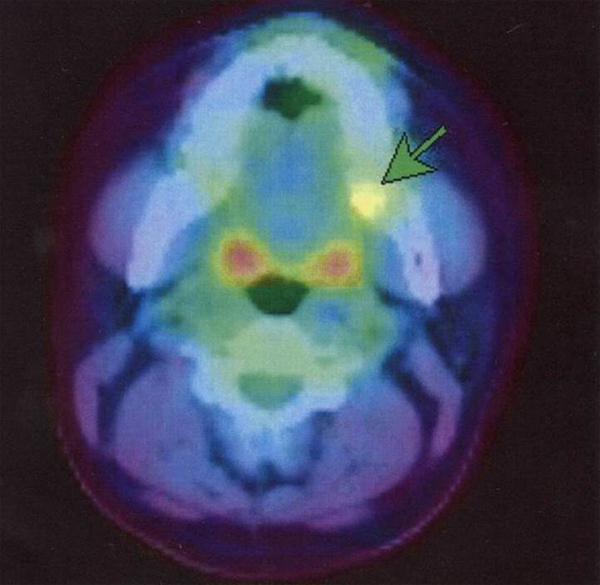

下顎の臼歯部にできた3mmほどの小腫瘤

病理組織学的;腺癌

PET-CTで病変が描出されている。